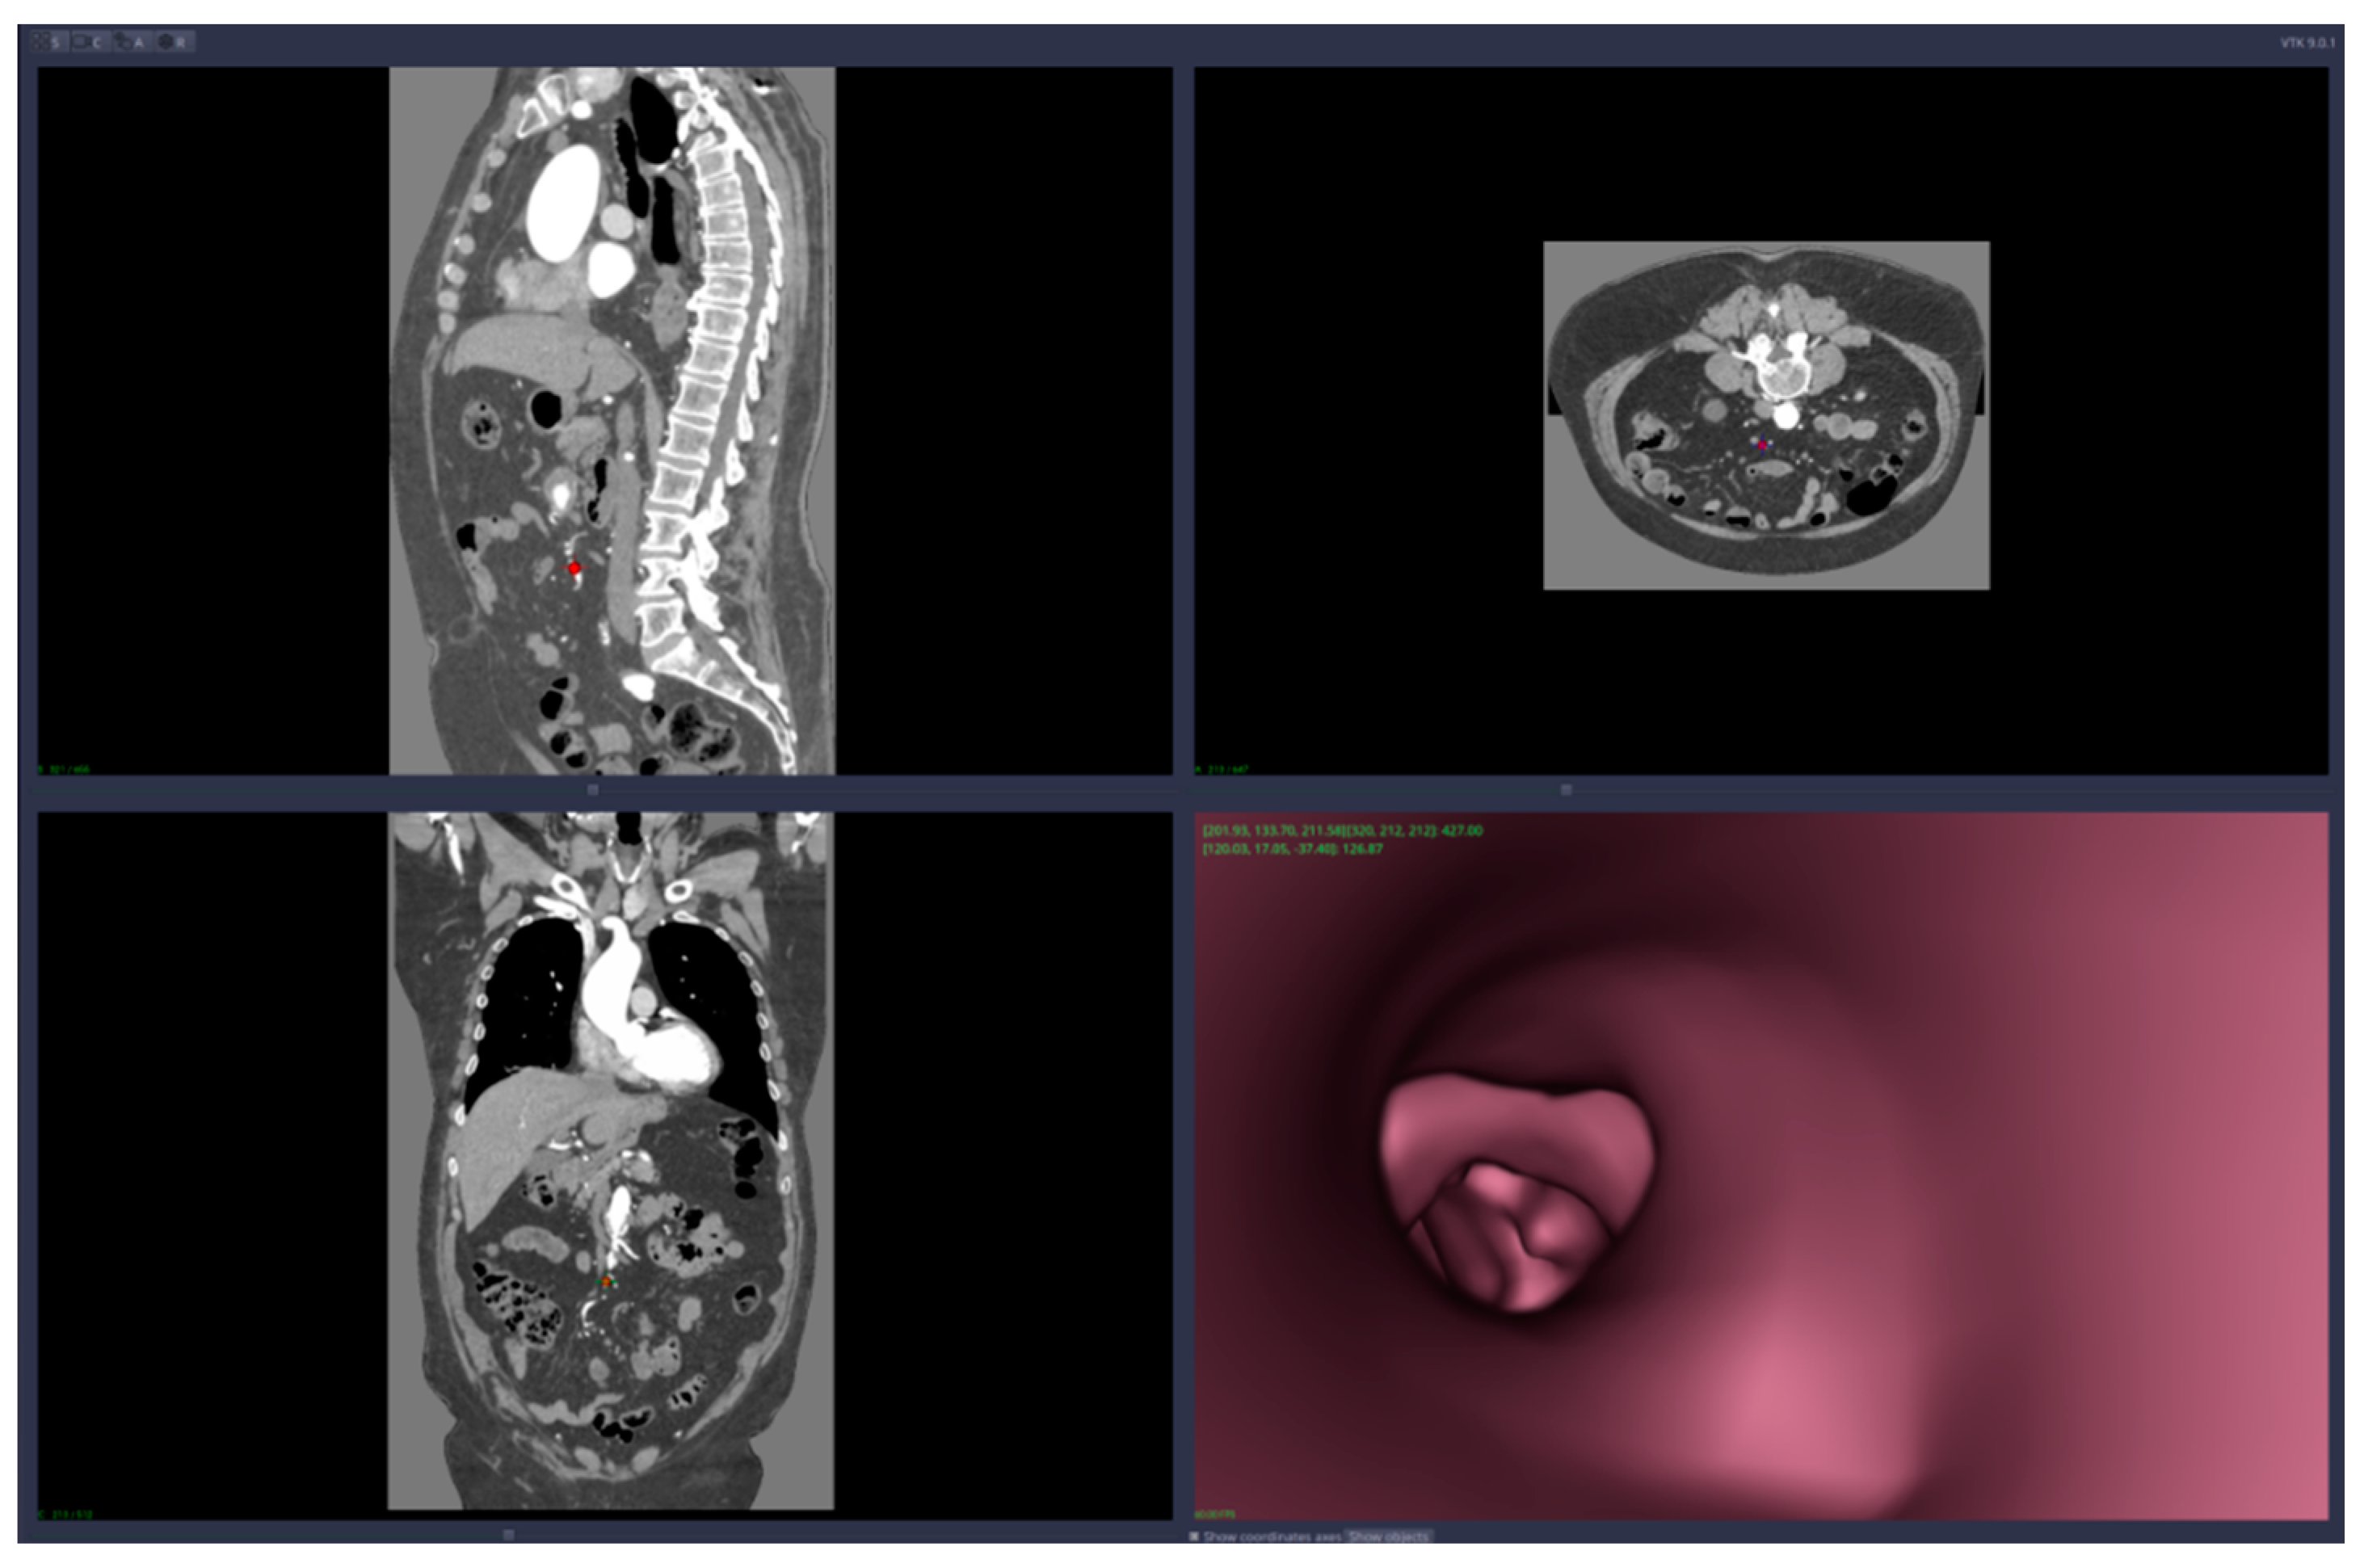

• Virtual angiography—virtual 3D navigation through the mesenteric artery and aneurysm zone (see Figure 3, Figure 4, Figure 5, Figure 6 and Figure 7)

Virtual angiography means that the user is able to navigate inside the artery using only the computer mouse device. The navigation starts from a point chosen by the user and the virtual camera is forced to remain inside the artery walls. The algorithm that implements this restriction on the virtual camera is based on collision detection and resolution directly on voxels (no segmentation is required). The path of the virtual angiography can be saved and used later, in other planning sessions.

Figure 5. Virtual angiography—“normal” zone of the mesenteric artery, after the aneurysm (direction is opposite to the blood flow).

Figure 6. Virtual angiography—exit from the mesenteric artery into the aorta (direction is opposite to the blood flow).